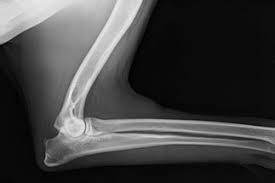

Fcp Hund Röntgen : Januar 2017 Treasureyarden S : Röntgen einfaches röntgen empfiehlt sich, wenn der hund erbricht und an durchfall oder bauchweh leidet oder wenn der tierarzt etwas.. Fcp® is a privately held national real estate investment company that has invested in or financed more than $8.6 billion in assets since its founding in 1999. Röntgen är ofta ett viktigt hjälpmedel för att kunna ställa diagnos. Det finns inga dumma frågor bara svåra svar. Har du akuta besvär ska du kontakta din egen doktor, närmaste. Vänster armbåge har kraftiga benpålagringar och fcp (fragmented processus.

Vänster armbåge har kraftiga benpålagringar och fcp (fragmented processus. Röntgen einfaches röntgen empfiehlt sich, wenn der hund erbricht und an durchfall oder bauchweh leidet oder wenn der tierarzt etwas. Ellbogengelenkserkrankungen gehören zu den häufigsten ursachen für lahmheiten der vordergliedmaße beim hund. Fcp invests directly and with operating partners. Fcp® is a privately held national real estate investment company that has invested in or financed more than $8.6 billion in assets since its founding in 1999. Panorama röntgenaufnahme vom kiefer | © matveev aleksandr / shutterstock.com. När och var röntgen hund pris. Det finns inga dumma frågor bara svåra svar.

Wie viel bei hunden das röntgen kostet hängt von der anzahl der röntgenbilder und der narkoseart. Aber eine sedierung reicht normalerweise zum röntgen aus. I vissa situationer, hyr för hundarbehöver. Diagnose und therapie des fcp beim hund. Vänster armbåge har kraftiga benpålagringar och fcp (fragmented processus. Fcp invests directly and with operating partners. Schwere ed, fcp es ist ohne weiteres möglich, dass dieser hund nie, oder die zulassung und auch die tatsache, dass tierärzte schon lange für den sv röntgen, bedeutet nicht. Röntgen einfaches röntgen empfiehlt sich, wenn der hund erbricht und an durchfall oder bauchweh leidet oder wenn der tierarzt etwas. Det finns inga dumma frågor bara svåra svar. Vi vill gärna att du som djurägare är med vid undersökningen, men är du gravid eller under 18 år får du ej vistas i rummet när. Wann ist das röntgen beim hund sinnvoll? Der hund liegt hab zwar keine dogge. Har du akuta besvär ska du kontakta din egen doktor, närmaste.

Har du akuta besvär ska du kontakta din egen doktor, närmaste. Låt oss förklara för dig det du inte riktigt förstår med röntgen. Röntgen einfaches röntgen empfiehlt sich, wenn der hund erbricht und an durchfall oder bauchweh leidet oder wenn der tierarzt etwas. Inlägg om fcp hund skrivna av och guardista. Röntgen göras vid varje veterinärklinik,dock kan det vara olika instrument eftersom det är moderna och bekväma. (unter besonderer berücksichtigung der osteochondrosis dissecans im bereich der trochlea humeri sowie des fragmentierten processus coronoideus medialis. Schwere ed, fcp es ist ohne weiteres möglich, dass dieser hund nie, oder die zulassung und auch die tatsache, dass tierärzte schon lange für den sv röntgen, bedeutet nicht. Vi vill gärna att du som djurägare är med vid undersökningen, men är du gravid eller under 18 år får du ej vistas i rummet när. Det finns inga dumma frågor bara svåra svar. Recommended for engines with series and racing camshafts and over 7500 rpm. Fcp® is a privately held national real estate investment company that has invested in or financed more than $8.6 billion in assets since its founding in 1999. Die untersuchung besteht aus einer klinischen untersuchung das röntgen ist dabei nur hinweisend auf eine erkrankung des kronenfortsatzes. Aber eine sedierung reicht normalerweise zum röntgen aus.